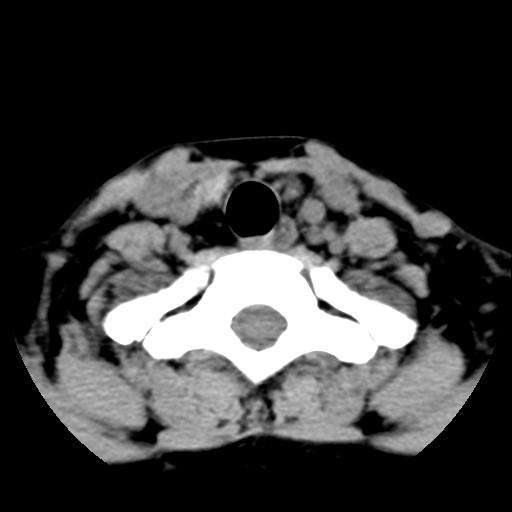

女,44岁,左颈部肿块伴疼痛两个月。患者不能做增强扫描。

左侧甲状腺明显肿大,密度不均匀性减低,正常之钙化基本消失,残留少许呈云雾状及颗粒状。其边缘不规则、不清晰,与前部联合处正常甲状腺不能分界不清,但尚可与周围其他组织分辨。颈动脉鞘区无明显淋巴结肿大。

多考虑:左侧甲状腺癌。

左侧甲状腺腺瘤或癌。甲状腺周围软组织间隙尚存在,喉软骨未见破坏征象,考虑腺瘤可能性大。

左侧甲状腺明显肿大,密度不均匀性减低,可见明显淋巴结肿大.

考虑:左侧甲状腺癌

左侧甲状腺弥漫性肿大,密度减低,与气管及周围血管等分界清晰,颈部未见明显淋巴结肿大.首先考虑左侧甲状腺瘤;其次考虑甲状腺炎;不排除甲状腺癌可能.

多考虑甲壮腺腺瘤可能性大,周边的脂肪间隙显示尚清楚,未见明显肿大淋巴结.气管未见受压.